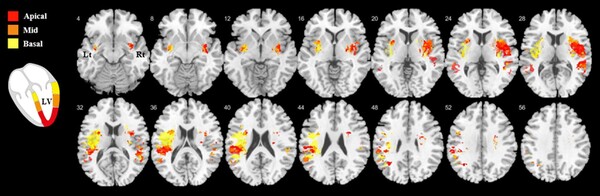

그 결과, 급성 허혈성 뇌졸중 환자 뇌의 우측 뇌섬엽(insula)와 주변 영역과 좌측 정수리 피질(parietal cortex)이 손상된 좌심실의 전반적인 종축 움직임 변화(left ventricular global longitudinal strain)와 관련이 있는 것으로 확인됐다.

더불어 손상된 좌심실 국소 종축 움직임 변화(left ventricular regional longitudinal strain)의 분포 패턴은 관상동맥 영역과는 별개로, 좌심실의 정점(apex)에서 기저부로 갈수록 관련된 뇌 병변의 위치는 우반구(right hemisphere)의 경우 우측 뇌섬엽의 부리쪽(rostral)에서 꼬리쪽(caudal)으로, 좌반구(left hemisphere)의 경우 두정(parietal) 영역에서 측두(temporal) 영역으로 이동하는 지형학적 연관성을 확인했다.

연구팀은 또 좌심실의 전반적인 종축 움직임 변화(global longitudinal strain)와 국소 종축 움직임 변화(regional longitudinal strain)와 관련된 뇌 영역을 분석함으로써 특정 뇌 피질 부위에 좌심실 수축성과 관련된 지형학적 표현(topographical representation)의 존재에 대한 시각적 증거를 제시했다.